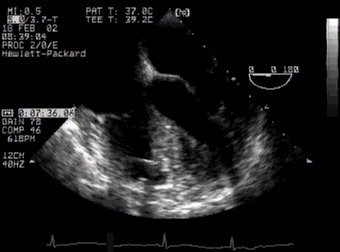

4. UP Basal view - coronary arteries echo: left coronary artery origin (basal)

In the anatomical section, both coronary arteries can be fairly well seen coming off the aorta (Ao), the left (lca) running laterally and the right (rca) in between the pulmonary artery (Pa) and right atrial appendage (raa). The superior vena cava (svc) also now comes into the picture. In the upper TOE picture, only the left coronary artery can be seen, at a slightly greater magnification; in the lower picture, you can see just the RCA. right coronary artery